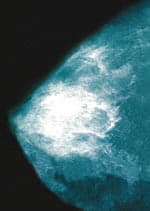

Cancer-Preventive EffectsAs early as 1961, low levels of CoQ10 were noted in patients with myeloma, lymphoma, and cancers of the breast, lung, prostate, pancreas, colon, kidney, head, and neck.16 However, CoQ10’s potential value in preventing breast cancer did not become apparent until more than three decades later, in studies conducted by Knud Lockwood, MD, a cancer specialist in Copenhagen, Denmark.24 Lockwood’s treatment of 32 “high-risk” breast cancer patients with antioxidants and other nutrients, including a daily dose of 90 mg of CoQ10, produced remarkable results. Although four deaths were expected, no deaths occurred. The subjects also reported decreased use of painkillers, an absence of weight loss, and an improved sense of well-being. Of the 32 participants, six showed partial tumor remission and two benefited from an even higher dose of CoQ10. One woman experienced a stabilized tumor when taking 90 mg of CoQ10; after her daily dose was increased to 390 mg, the tumor disappeared, a finding confirmed by mammography.24 Another patient who had a small tumor removed from her right breast refused to undergo a second operation to remove another. Instead, she began taking 390 mg of CoQ10 daily. Three months later, mammography confirmed an absence of tumors or metastasis in her breast.25 In a follow-up study more than one year later, three other subjects in the original study who had combined conventional cancer therapy with CoQ10 supplementation of 390 mg a day also saw their tumors disappear with no evidence of metastasis.26 CoQ10 thus appears to be the dominant nutrient contributing to breast cancer regression and prevention of its recurrence.25 Correcting a CoQ10 deficiency may be essential for good health. According to Stephen Sinatra in his book The CoQ10 Phenomenon, “Without CoQ10, the body cannot survive.”10 Sinatra recommends CoQ10 supplementation, especially for those undergoing breast cancer therapy and others who are at risk of having depleted stores of CoQ10, including aging adults and users of cholesterol-lowering statin drugs.10 | |||||||